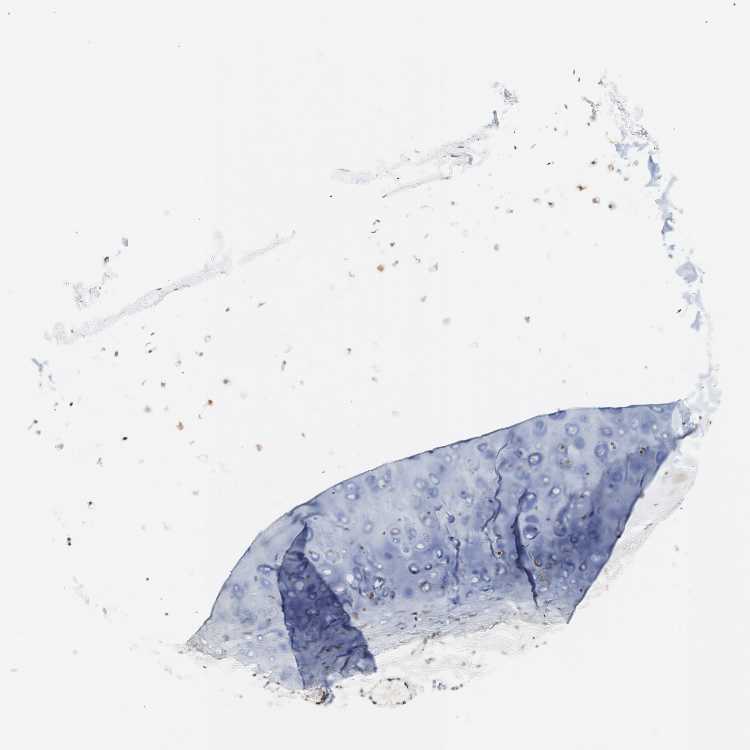

SOFT TISSUE 1 - Antibody stainingi

Antibody staining in the annotated cell types in the current human tissue is reported as not detected, low, medium, or high, based on conventional immunohistochemistry profiling in selected tissues. This score is based on the combination of the staining intensity and fraction of stained cells.

Each image is clickable and will lead to virtual microscopy that enables deeper exploration of all samples and also displays staining intensity scores, fraction scores and subcellular localization as well as patient and tissue information for each sample.

Antibody HPA003909Antibody CAB009021

Chondrocytes Low-

Fibroblasts MediumMedium